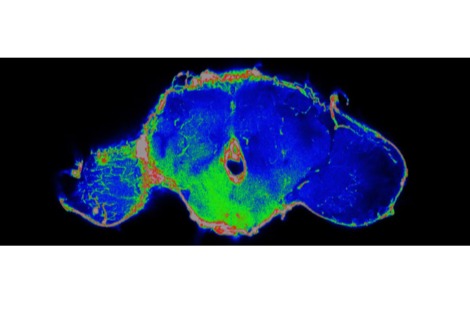

في دراسة جديدة نُشرت اليوم (23 مارس) في مجلة eNeuro، ركّز الباحثون على كبار السن، سواءً المصابين بمرض باركنسون أو غير المصابين به. ووجدوا أن هاتين المجموعتين تُنتجان إشارات دماغية أقوى ونشاطًا عضليًا أكبر حتى أثناء اضطرابات التوازن الطفيفة. ووفقًا لتينغ، "يتطلب استعادة التوازن طاقةً وجهدًا أكبر من الدماغ لدى هذه الفئات. وقد وجدنا أنه عندما يحتاج الأشخاص إلى مزيد من النشاط الدماغي للحفاظ على توازنهم، تقل قدرتهم على استعادة توازنهم".

كما لاحظ الفريق أنه عندما يُفعّل كبار السن عضلةً ما لتثبيت أنفسهم، تنقبض العضلات المقابلة في الوقت نفسه. هذه الصلابة الإضافية تُقلل من سلاسة الحركة وترتبط بضعف أداء التوازن.